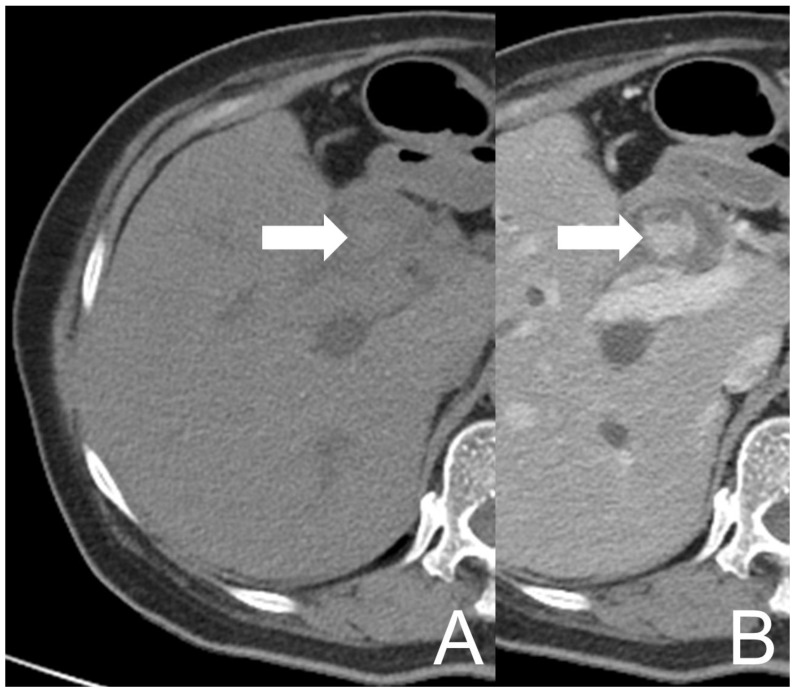

However, her symptoms recurred four months later. She visited our Emergency Department again where the abdominal CT showed an intramural lesion in CHD and CBD with mixed high and low densities and heterogeneous enhancement, accompanied with dilatation of the biliary tract (Figure 2). The picture was similar to that on the prior MRCP. She was treated as cholangitis and ERCP biopsy was redone for the neoplastic survey. During the procedure, CBD dilation with tissue retention and papillary mucosal surface were noted. Similar to the prior pathological report, descriptive diagnosis illustrating blood clots, histiocytes and some multinucleated giant cells aggregate was made. Antibiotics were used to treat the patient effectively.